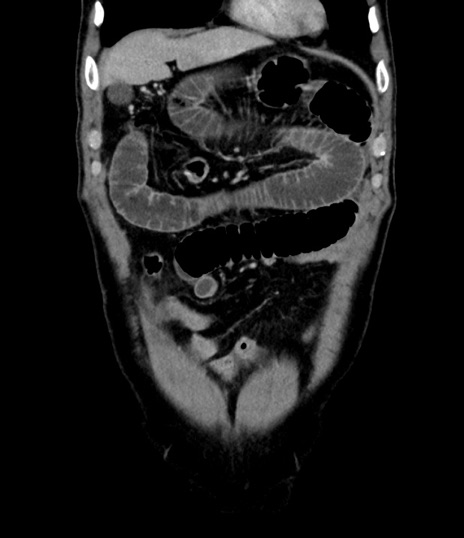

症例8(冠状断像)

【症例】 60歳代男性

【主訴】 黒色吐物

【現病歴】 4日前から嘔気自覚、2日前の朝食後にも嘔気あり、自分で手で嘔吐反射起こし嘔吐したところ血が混ざっていたため受診。

【既往歴】 5年前汎発性腹膜炎を伴う急性虫垂炎で手術、高血圧、前立腺肥大症、高脂血症

【身体所見】 腹部正中に手術癩痕あり 腹部平坦・軟圧痛なし膨満感あり

【データ】WBC 8400、CRP 4.54